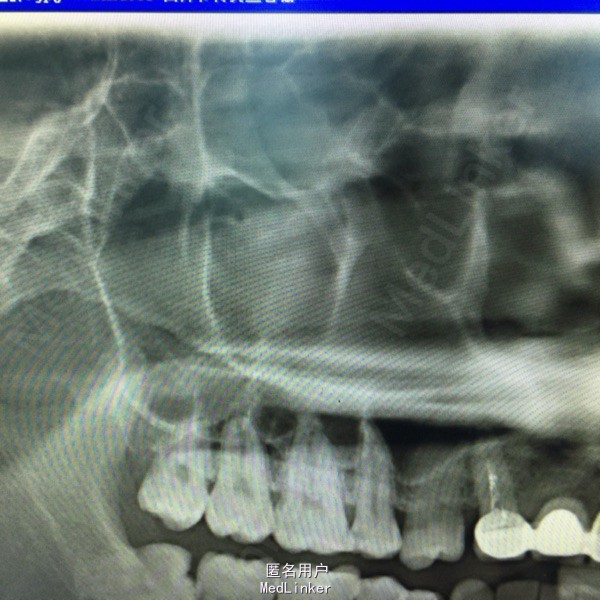

上前牙烤瓷冠修复,13牙冠缺损,叩(+),行桩冠修复。曲面断层片示:13、14根尖可见4x2cm阴影,边缘可见白色阻射线。

诊断:13、14根尖囊肿 处理:1、拆除桩冠。 2、13行牙髓治疗。 3、囊肿行开窗引流术。

患者每天以生理盐水冲洗,2一4次/天,半年复查X片。 该患者1年半后,可见囊腔缩小,新骨长入。无需行囊肿挖除术。